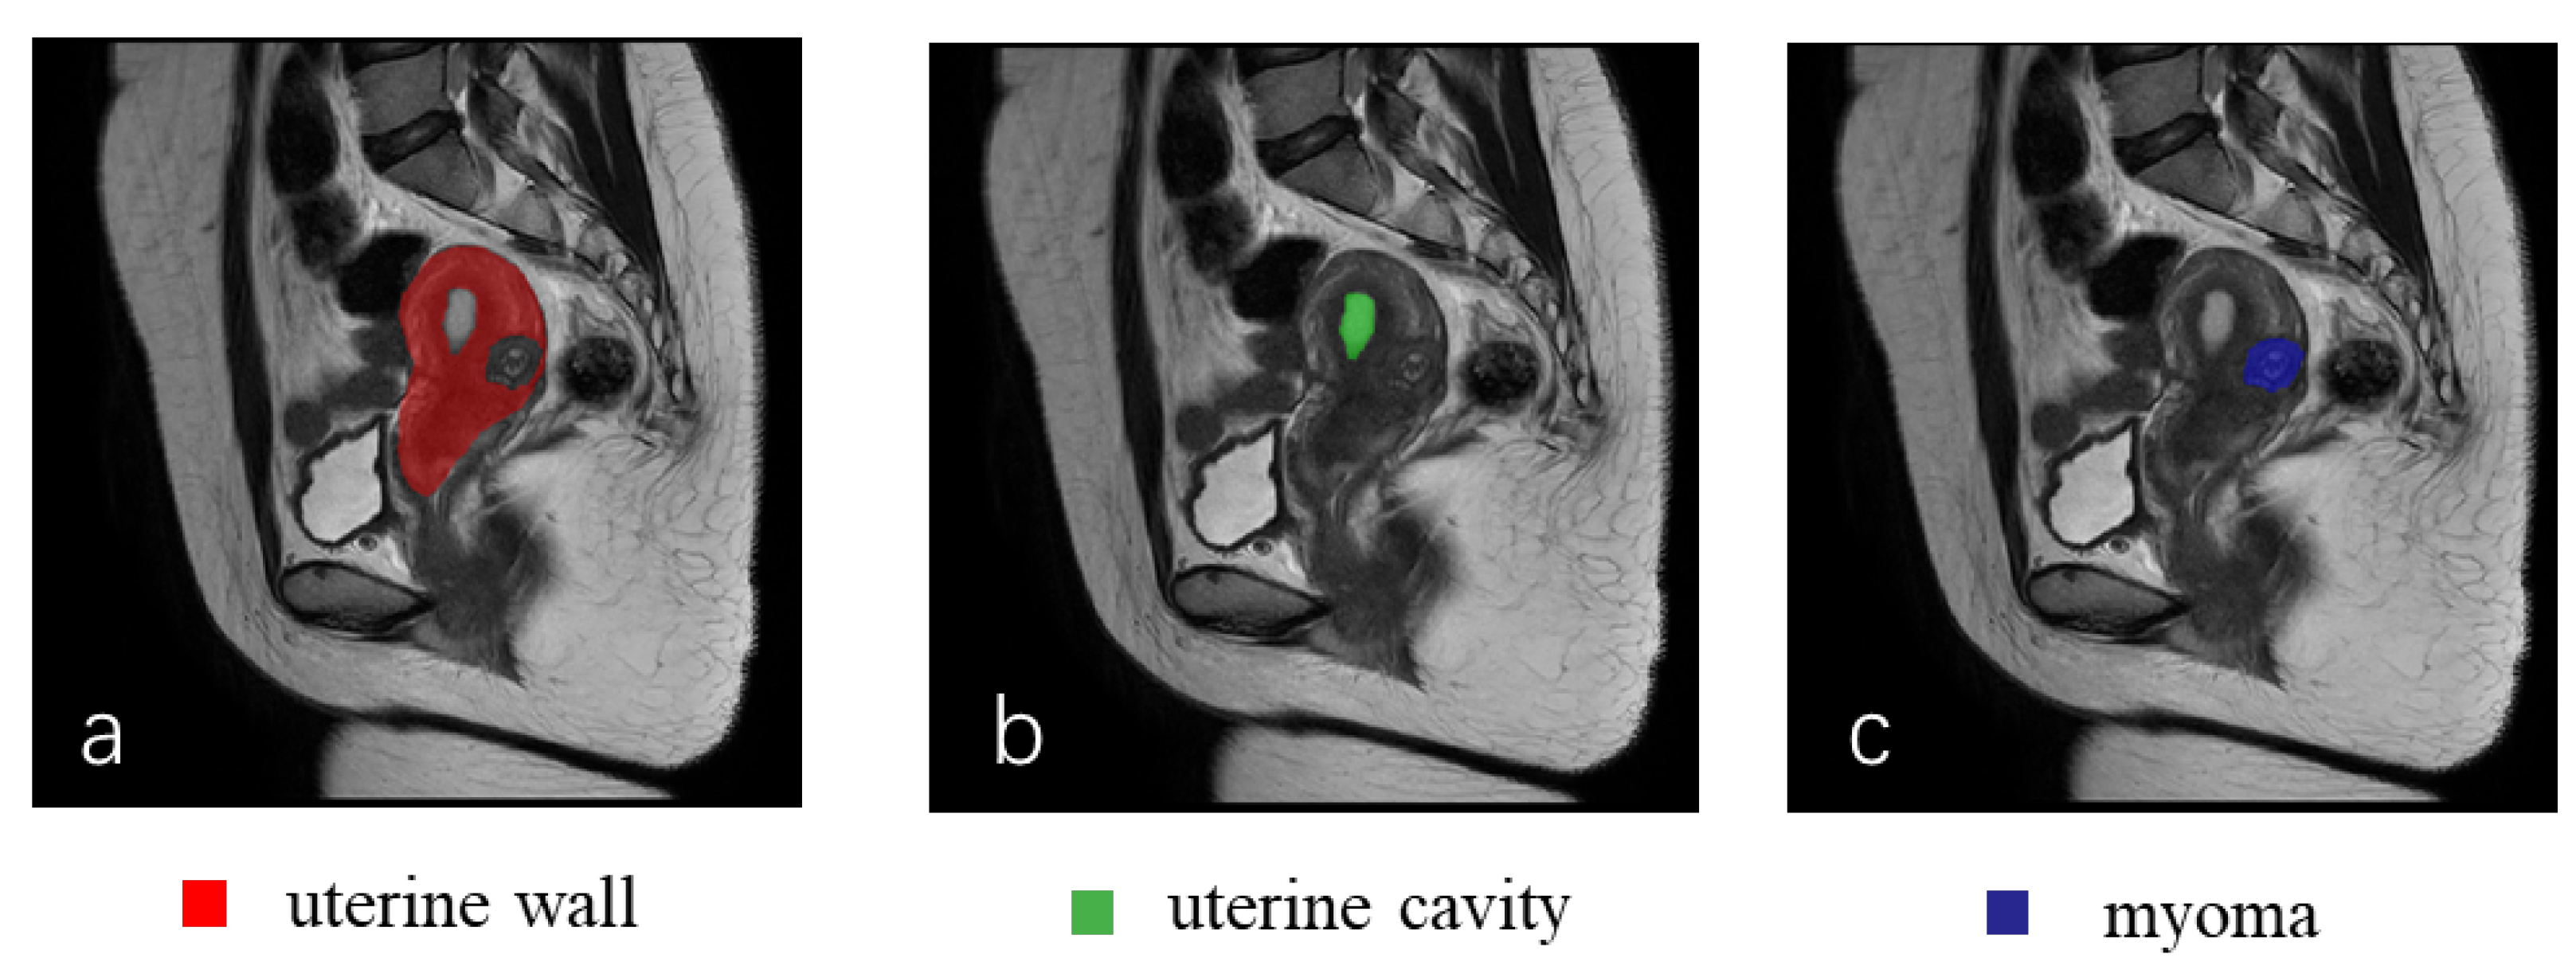

2.1. Dataset Description

2.1.2. Image Preparation and Preprocessing